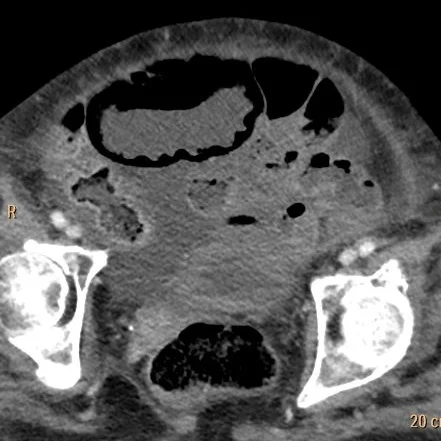

Conventional CT: Extensive pnematosis.